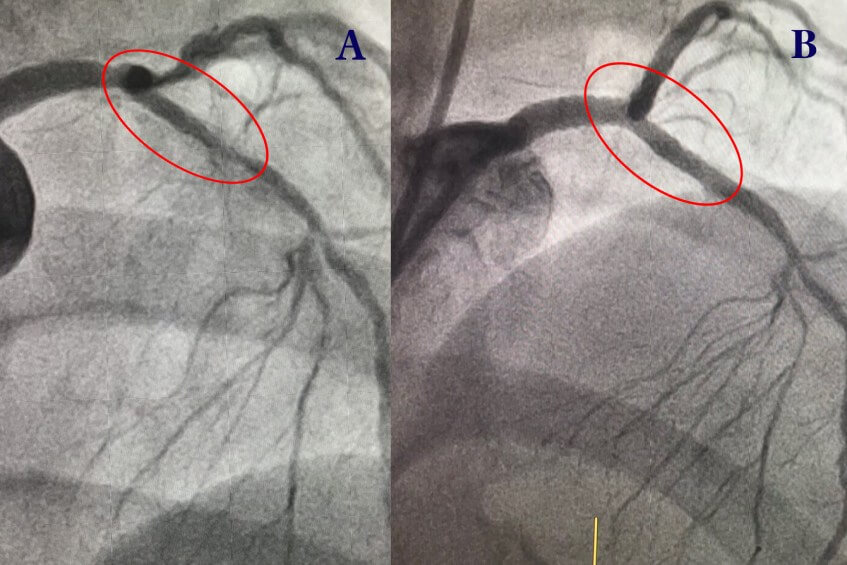

Bà Trần Thị Tâm (60 tuổi) kiểm tra sức khỏe tại Bệnh viện Đa khoa Tâm Anh TP HCM khi có dấu hiệu đau ngực, cảm thấy khó thở khi gắng sức. Bà có sử dụng thuốc nhưng không cải thiện. Qua chụp mạch vành với lượng thuốc cản quang tối thiểu (Cardiac Swing), bác sĩ kết luận bệnh nhân bị hẹp mạch vành lan tỏa, kéo dài từ vị trí thân chung động mạch đến đoạn liên thất trước, đoạn hẹp nhất lên đến 90%. Bà Tâm mắc bệnh nền đái tháo đường, tăng huyết áp, rối loạn mỡ máu.

Từng đợt khoan kéo dài từ 5-10 giây hoặc từ 10-15 giây diễn ra để đảm bảo trái tim được tưới máu liên tục, các mảng xơ vữa vỡ vụn với kích thước nhỏ hơn hồng cầu. Cuối cùng, bác sĩ mài bề mặt lòng động mạch nhẵn, trơn trước khi tiến hành đặt stent cho bệnh nhân. Sau một giờ, mạch máu của bệnh nhân được mở rộng đến 4.5 mm tại vị trí thân chung động mạch, đạt kích thước 3.5 mm ở đoạn động mạch liên thất trước. Bệnh nhân khỏe mạnh, hồi phục nhanh, xuất viện sau 2 ngày.